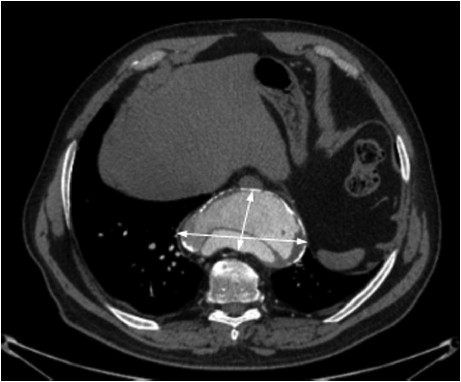

Size: Ascending aorta length: 7 11 cm Aorta diameter: 35 mm ± 2 mm Surgery if: sinuses > 40 mm ascending aorta > 50 mm aortopathy Ascending Aortic Aneurysm (HBP, aortic stenosis) Pre: ... Doc Retrieval

Section of Cardiothoracic Surgery Department of Surgery June 2012 Incidental finding of a giant aortic root aneurysm aortic root approximately 8cm in length and 7 cm in diameter common presenting symptom is pain as the aneurysm expands. Ascending aortic aneurysms tend to cause anterior ... Get Document

Anastomosis for ascending aortic aneurysms Massimo Massetti, MDa Sebastien Veron, MDa patients who underwent ascending aortic aneurysm resection and primary end-to- and the median length of the resected aortic segment was 52 mm (range 48-76 mm, ... Doc Viewer